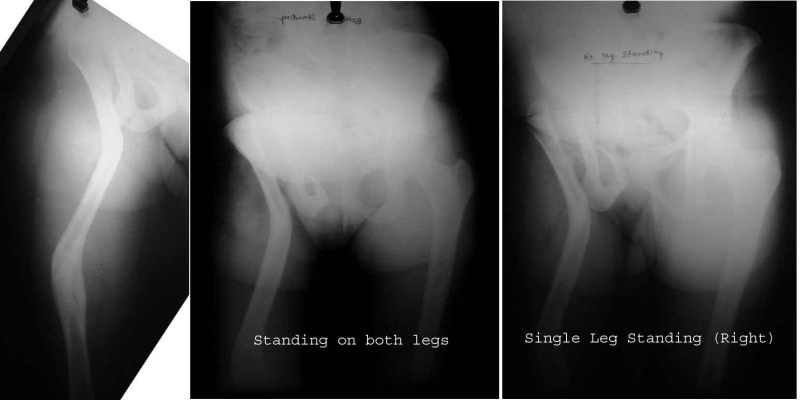

A 30-year-old female patient, presented with pain and limping post hip surgery and lengthening using Ilizarov technique 2 years duration.She said she had only limping preop. now she has painful limping and she can't walk without using walking aid.

Her X-ray --> non-union at the osteotomy site,pelvic tilt,bowing of the femur.clinically painful mobile pseudoarthrosis, LLD =4CM. Could those colleagues using such type of osteotomy Ilizarov method give us the clues how to treat such problems?Does this type of osteotomy still practiced by the group?Dr.Freih Odeh Abu Hassan,M.D(Orth.), F.R.C.S(Eng.), F.R.C.S.(Tr.&Orth.),Asst.Professor of Orthopedics Surgery,Jordan University - Amman.

This operation - the Ilizarov Hip Reconstruction consists of an extreme valgus osteotomy in the proximal femur, to stabilise the unstable hip, a lengthening distally to equalise the limb lengths, and a varusization thru that lengthening zone to bring back the distal limb parallel to the other limb, and normalise the "mechanical axis".

The bowing of the femur that you mention, is intentionally created thru the lengthening site as noted previously.

Attached are some pics of a case of an 18 year old girl with shortening and trendelenburg lurch, both of which were corrected by the procedure.

The xrays in single stance show that the pelvis continues to remain level, in the single stance, despite the absence of the head.